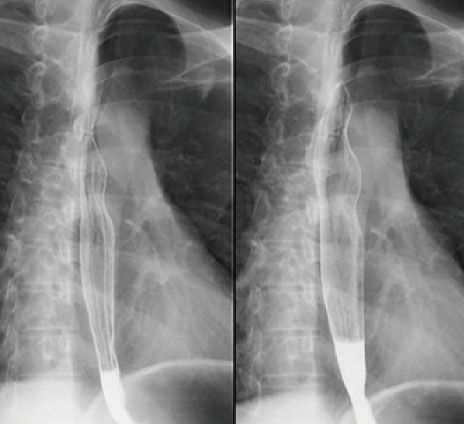

食道

胃

消化管造影検査では、上部消化管(胃・十二指腸・小腸)や下部消化管(大腸)に対し、バリウムやガストログラフィンなどの造影剤を付着させ、検査します。さらに空気で消化管を膨らませ、体位変換によって造影剤、空気を移動させ、病変が粘膜のひだや腸管の重なりで埋もれてしまわないように検査を行っています。胃や腸を広く観察できるため、病変の場所や大きさなどがわかります。